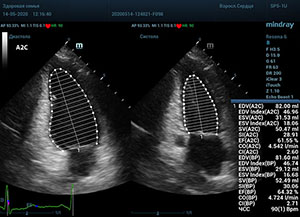

С появлением В режима реализовалась возможность визуализации всех сегментов миокарда из парастернальных и апикальных сечений. Метод Teicholtz в широкой практике сменился методом дисков. Метод дисков, или метод Simpson, позволяет разбить левый желудочек на 20 дисков, с расчетом объема каждого из них. Используя 2 перпендикулярных сечения, апикальные двух и четырех камерное, мы приближаемся к значению реального объема левого желудочка. Исследователь обводит интерфейс эндокард – кровь в фазу диастолы и фазу систолы. Линия простирается от кольца митрального клапана и до кольца митрального клапана, четко разграничивая объем желудочка от предсердия. Для достоверного изменения необходимо использовать ЭКГ канал.

Обводить вручную эти линии занимало много времени, однако результат того стоил. Следующим шагом стало появление Spline технологии, позволяющее расставлять точки и автоматически их соединять. Такой способ планиметрии контура эндокарда значительно сократил время измерения.

Что могут предложить современные приборы? Приборы нашего времени являются мощными вычислительными машинами, способными обрабатывать полученную информацию даже без помощи человека. Система автоматического вычисления фракции выброса – AUTO EF на приборах серии Resona компании Mindray сделает все за вас. За пару секунд прибор сам отыщет нужную фазу сердечного цикла и произведёт измерение и расчеты, а также покажет график изменения объема в сердечном цикле. От Вас требуется только получить качественное 4С и 2С сечение. Впрочем, прибор всегда оставляет возможность коррекции, если доктор имеет свое мнение на расположение точек планиметрии или момента измерения по ЭКГ каналу.